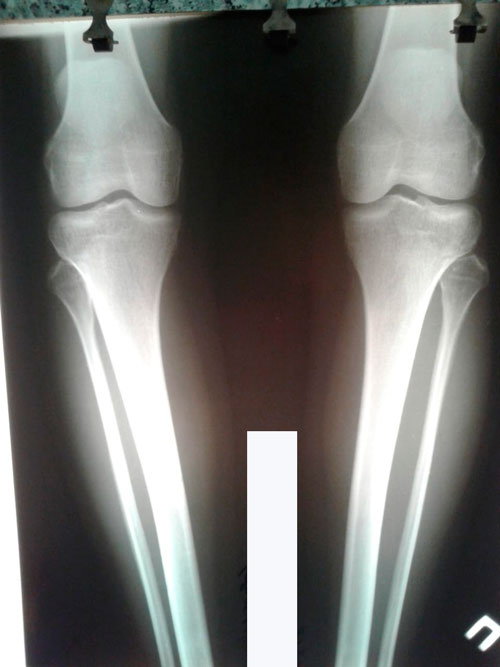

Дата операции 04.07.2018г.

Дата снятия аппаратов 16.10.2018г.

Срок сращения - 102 дня.

IMG-20180703-WA0007.jpg

IMG-20180703-WA0009.jpg